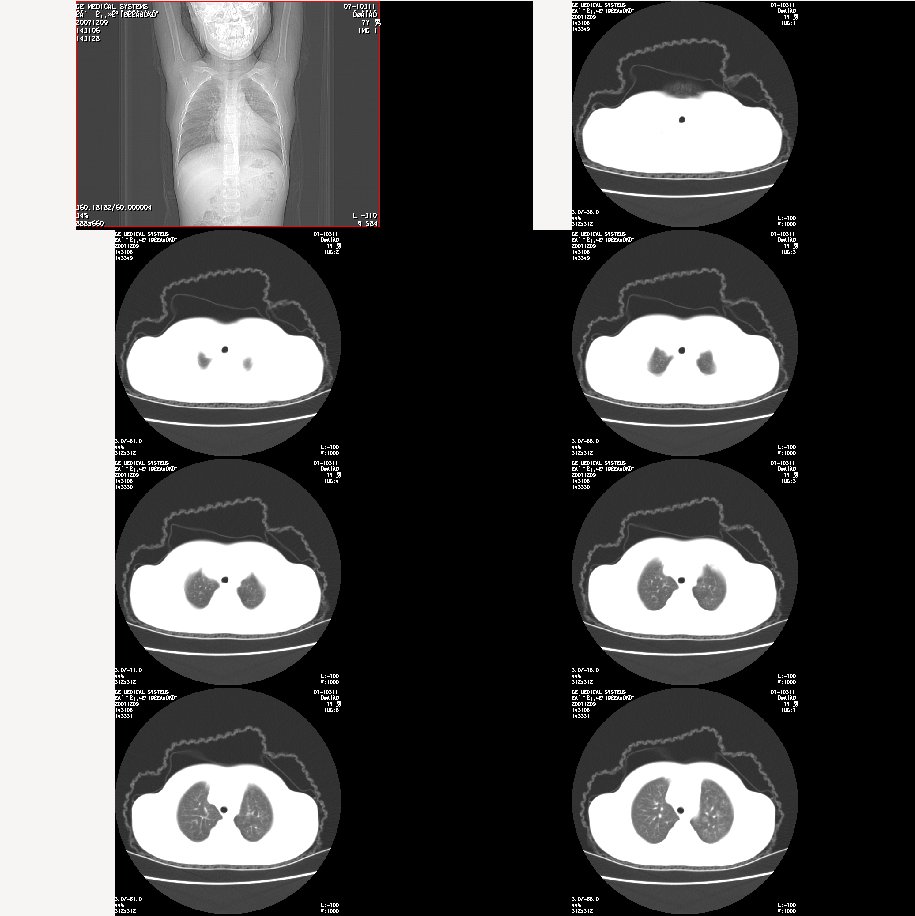

m 7

咳嗽、咯血半月。查体:双肺呼吸音粗,可及干湿鸣。自诉每年均有发作。

肺窗:

图像太小了,不好看,左肺出血、感染性病变?

双肺感染性病变——结核可能性大!

炎症应该有,排除一下有没有支扩吧

左肺上叶上舌段不张实变,建议纤支镜检查

支持 肺发育不全伴感染与支气管扩张